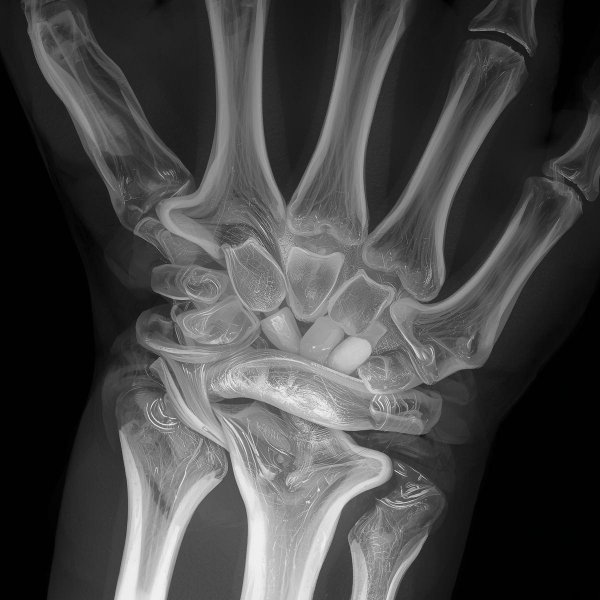

Imagerie

L’imagerie n’est pas systématique.